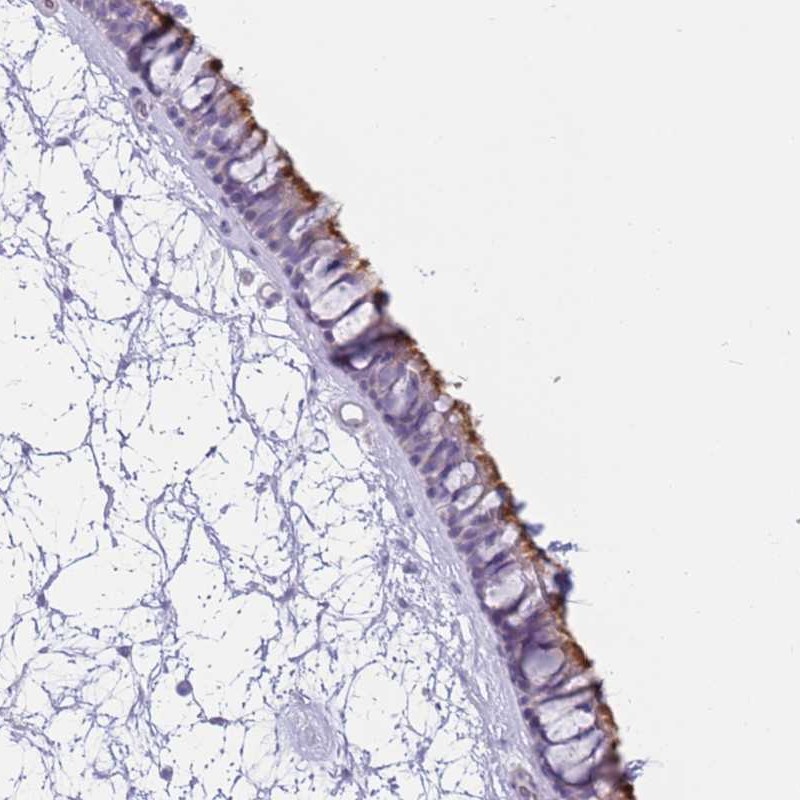

Immunohistochemical staining of human nasopharynx shows strong positivity in cilia of respiratory epithelial cells.